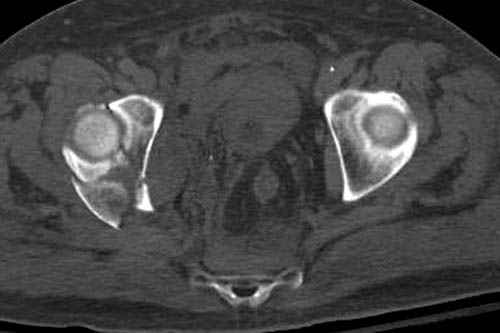

Дополнительно имеется перелом ацетабулума: задняя

колонна с полупоперечным переломом, и переломы костей лица.

На седьмой день зафиксирован перелом ацетабулума через задний доступ. Перед операцией для профилактики DVT, IVC фильтер, также получает Lovenox.

Снимки здесь....